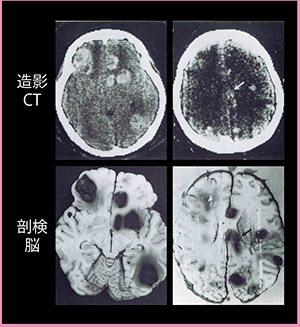

MK-1での最初の症例は,手術予定だった悪性黒色腫の多発性脳転移の患者に対する造影CTだった(図3)。CTによって脳内の多数の腫瘍と周囲の浮腫が見られた時は,放射線科医や脳神経外科医が,初めて脳の内部を見た驚きの瞬間だった。その後,剖検された脳の標本と比べると,病態が進んで腫瘍が大きくなってはいるものの,CT画像の正確さが証明された。

図3 1975年8月26日に撮影された

日本で最初のCT画像